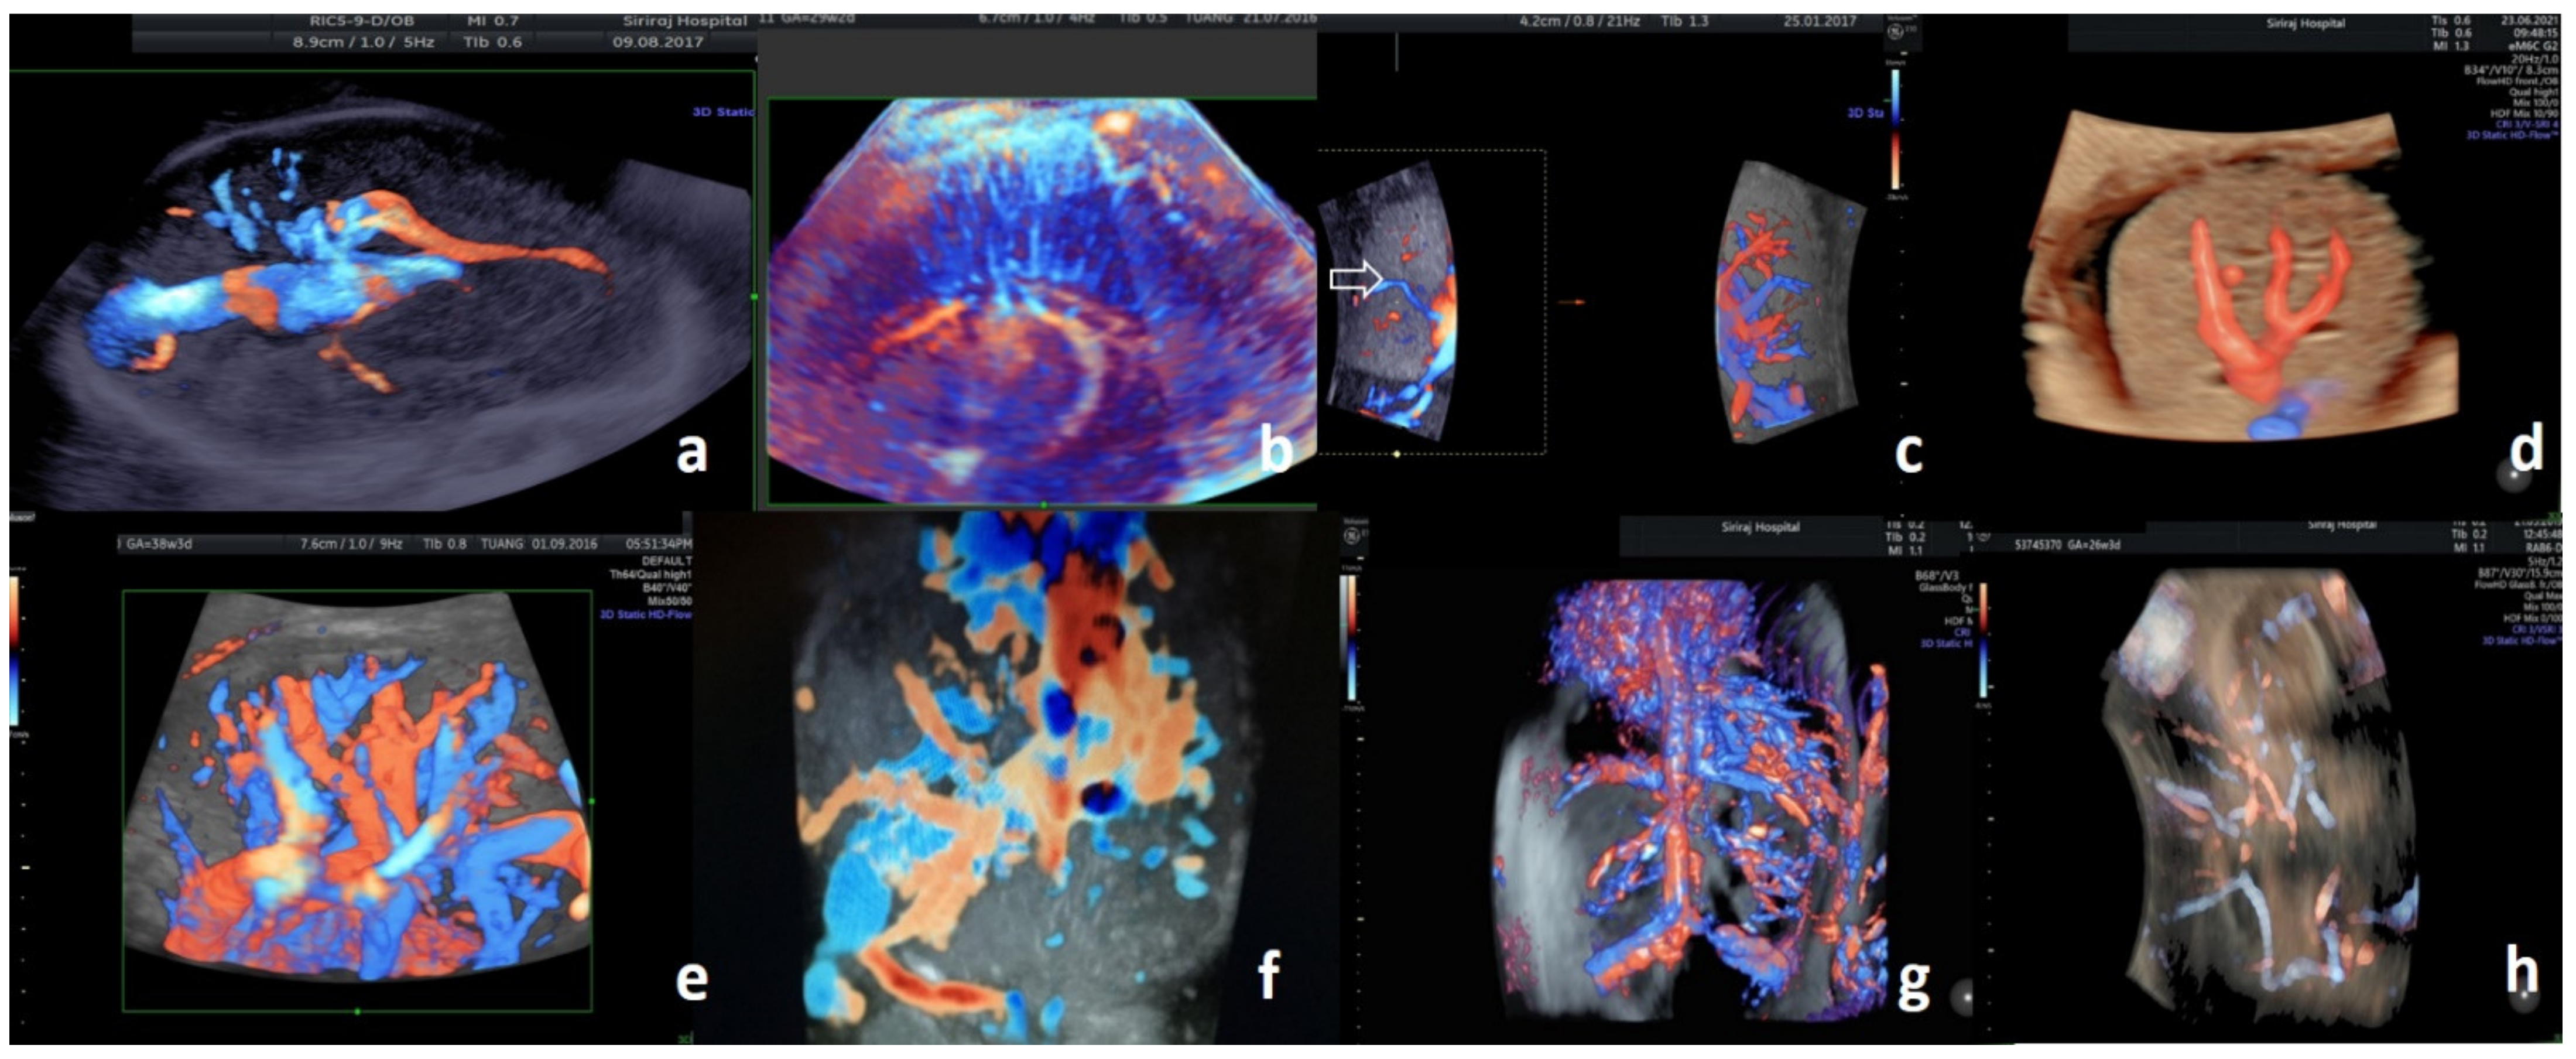

3.1. Fetal Central Nervous System

3.2. Fetal Intrathoracic and Intra-Abdominal Viscera

3.3. Fetal Mediastinal and Retroperitoneal Great Vessels

3.4. Fetal Tumors

3.5. Placenta

3.6. Umbilical Cord